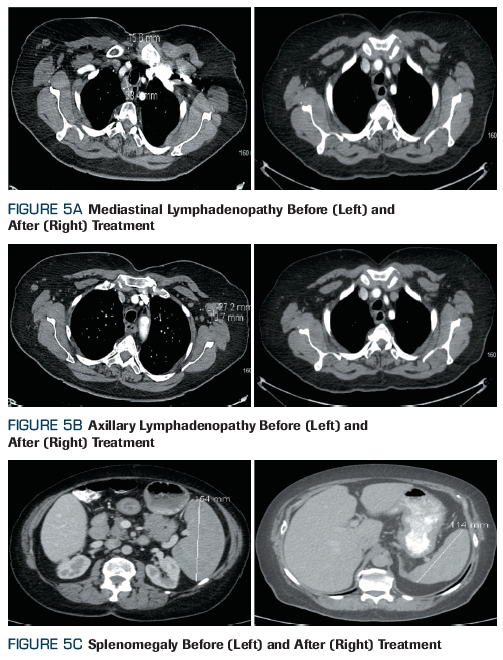

或体重减轻。由于患者超重,体格检查未发现淋巴结肿大或器官肿大。进一步检查胸部、腹部和骨盆的CT扫描显示腋窝、肺门和纵隔淋巴结肿大,以及脾肿大(图5)。单侧骨髓穿刺和活组织检查显示边缘区淋巴瘤受累。患者接受6个周期的利妥昔单抗

(R-CVP)联合化疗,并获得完全缓解。

图 5